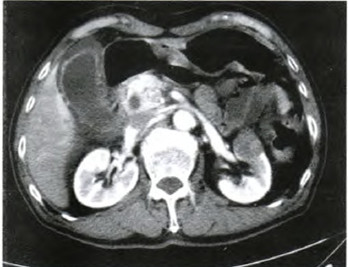

患者,男,77岁,全身乏力、出冷汗、头晕2天于2011年4月8日入院。B超显示胆囊体积增大,胆管扩张。诊断为胆道感染,给予抗炎治疗,病情好转。为排除泌尿系统感染,行双肾及输尿管CT扫描,结果显示:左肾中极前部见一大小约2.7cm×2.5cm异常肿块影,边界尚清,平扫时呈等低混杂密度,平均CT值约21HU,增强后动脉期呈明显不均匀强化,CT值约51HU,门脉期呈结节状更显著强化,CT值约73HU。影像学诊断:左肾中极前部占位,首先考虑肿瘤性病变(图1)。体格检查:肾区未触及肿块,无叩痛。于2011年4月1l号行左肾肿瘤剜除术。

图1 CT示左肾中极前部见一边界清楚的等低混杂密度的肿块影